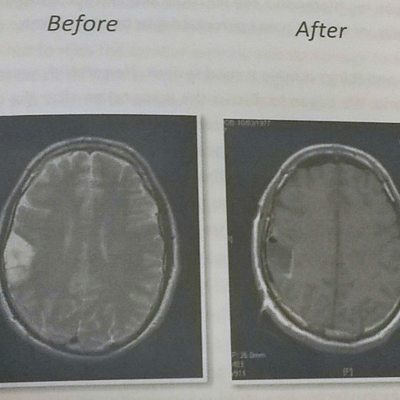

Dan, from Southampton, talks about undergoing brain surgery & becoming a dad to triplets